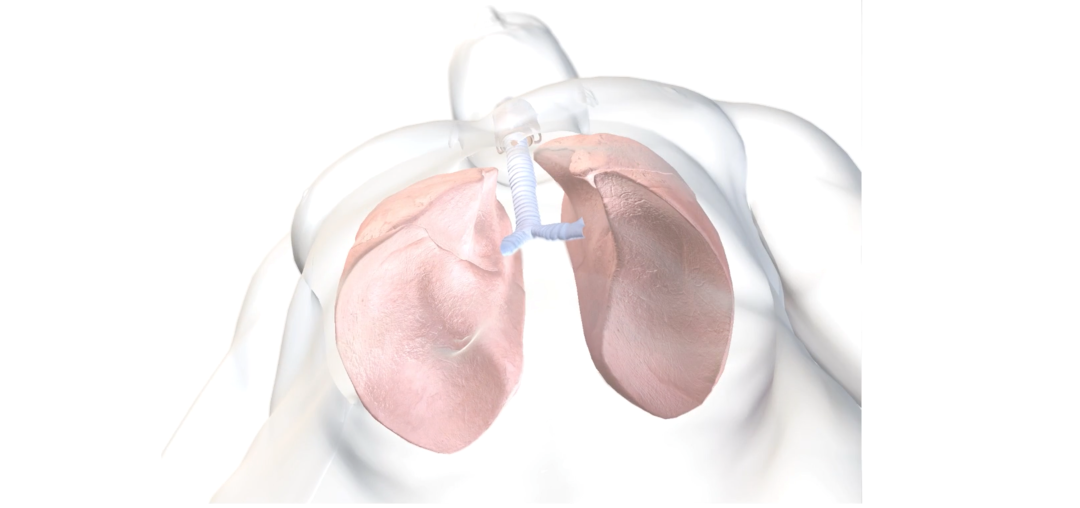

人体的肺是一对充满空气的器官,位于胸腔内,左右两侧各有半个肺脏,被中央纵隔隔开,其中包含心脏、胸腔大血管、胸腔气管、食道、胸腺及其他结构。

需要注意的是,由于心脏并未为对称结构,心脏向胸腔左侧延伸,对左肺的影响明显大于右肺,因此两个肺的解剖结构并不完全对称。每个肺都被一层称为胸膜的膜覆盖,胸膜又分为紧密附着在肺上的脏层胸膜和排列在肺腔内的壁层胸膜。它们之间是胸膜腔,通常充满一层薄薄的液体。

在每个肺的内侧部分,有肺门,肺根穿过这里。肺根由主支气管动脉和静脉等结构组成。